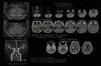

Subarachnoid hemorrhage (SAH) caused by a dissecting aneurysm of the anterior inferior cerebellar artery (AICA) is rare. Partial coil embolization of the AICA may be an effective treatment. A 65-year-old woman presented at the emergency room with headache and vomiting for the past five days, after contracting coronavirus disease (COVID-19). Computed tomography (CT) revealed SAH and intraventricular hemorrhage, and the patient was diagnosed with a dissecting aneurysm of the AICA. The patient underwent endovascular surgery, and the AICA was partially occluded using coiling, with no subsequent hearing disturbance, cranial nerve palsy, or infarction. Ventriculoperitoneal shunt surgery was performed for hydrocephalus at 7weeks after SAH. The patient was discharged from hospital with no neurological deficit. We reported a rare case of ruptured AICA dissecting aneurysm, which was treated by partial coil embolization without neurological deficit or infarction.